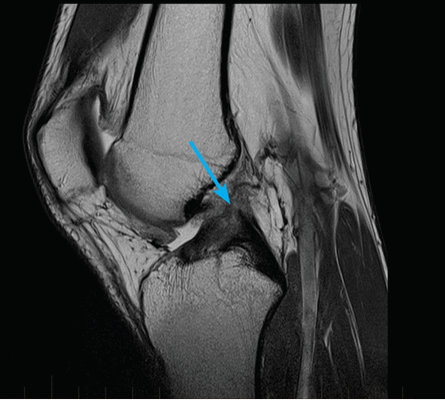

МРТ коленного сустава. Сагиттальная Т2-взвешенная МРТ. Повторный разрыв оперированного мениска.